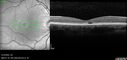

Dome Shaped Macula Left Eye158 views73 year old female Diagnosed with POHS in the past and treated with laser in the right eye in 1994 with vision loss. She moved from Tampa to Largo in 2017 and started seeing Dr. Cohen. She had her last injection in the left eye 2015 prior to moving to Largo. She has been treated intermittently in the left eye and has been resistant to Anti-VEGF injections. Her vision is good in the left eye. Images are from April 2023 one month following a Vabysmo injection in the left eye.

PMHx- thyroid disease

Meds: Synthroid

VA 20/200 OD, 20/25 OS